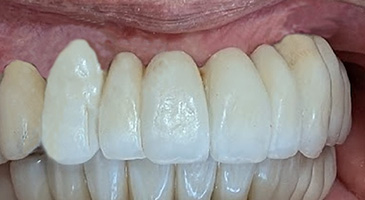

30年経過症例 / 92歳(2025年現在)・男性

1995年 上顎インプラント埋入時(61歳)

2002年 下顎インプラント埋入時(69歳)

92歳(2025年現在):シッカリ噛める事で咀嚼筋・表情筋が鍛えられ顔に張りがあり高齢にも拘らず縦ジワが全く見られません。最近まで車の運転をされていました。